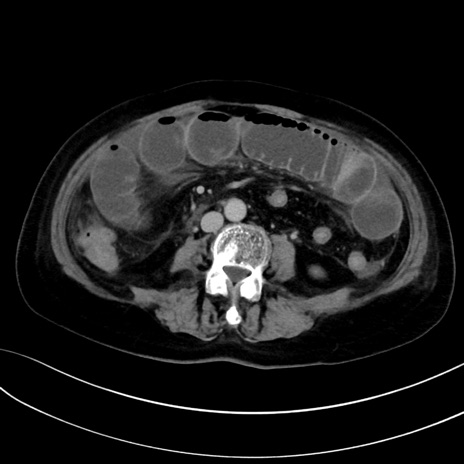

症例13 CT(横断像)1日半後